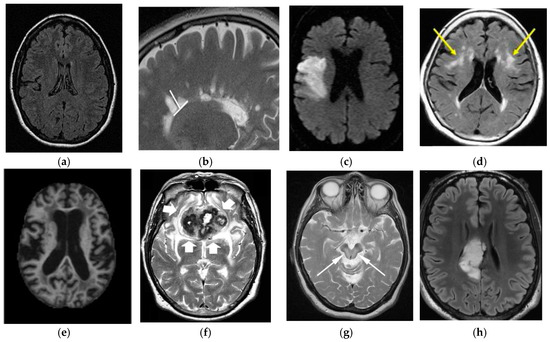

3.2. Magnetic Resonance Imaging

5.3. Imaging Test